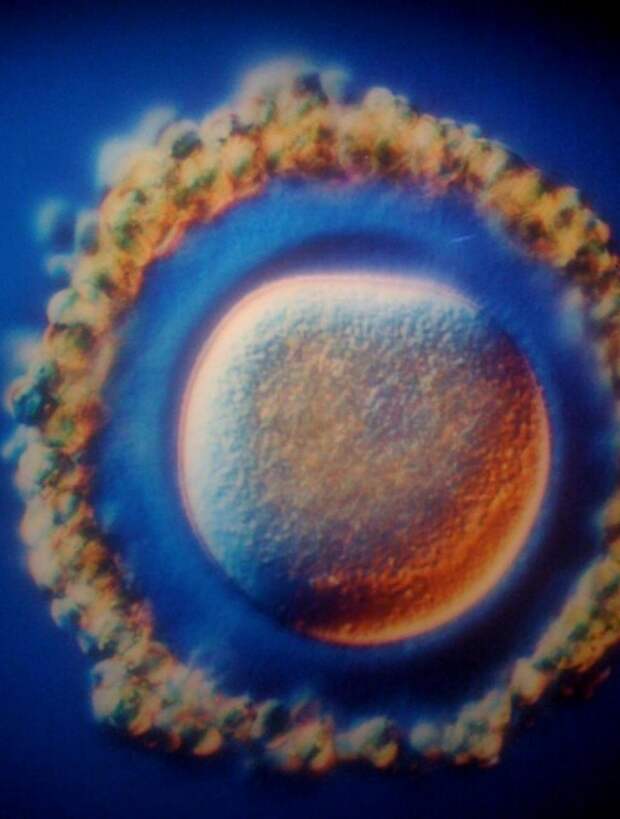

Дальше сперматозоид двигается по маточной трубе к яйцеклетке.  А это сама яйцеклетка, в ней сейчас зародится жизнь.

А это сама яйцеклетка, в ней сейчас зародится жизнь.  Брешь прорвана!